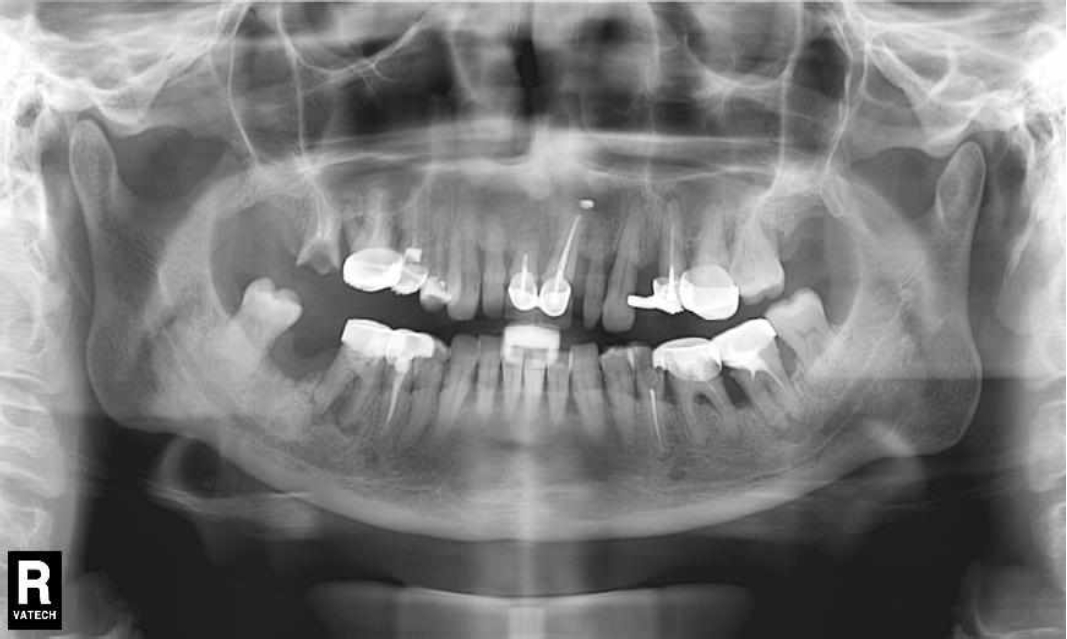

Ранее у пародонтолога не наблюдалась. При осмотре выявлены: неудовлетворительная индивидуальная гигиена полости рта, пародонтальные карманы до 7 мм, обильная кровоточивость и гноетечение из пародонтальных карманов, подвижность зубов 4.2, 4.1, 3.1, 3.2 II степени, обильные над- и поддесневые зубные отложения (рис. 1). На ортопантомограме отмечается резорбция костной ткани до ½ длины корня, очаги остеопороза (рис. 2). Пациенту был поставлен диагноз хронический генерализованный пародонтит тяжелой степени тяжести. При осмотре была составлена пародонтограмма с использованием компьютерного зондирования (рис. 3).

Рис. 3. Пародонтограмма с использованием компьютерного зондирования при первичном обращении

Через 6 месяцев при осмотре выявлен удовлетворительный уровень индивидуальной гигиены, отсутствие участков кровоточивости и гноетечения (рис. 4), пародонтальные карманы уменьшились в размерах (рис. 5). Пациент отмечает значительные улучшения. После стабилизации пародонтологического статуса пациент направлен для дальнейшего ортопедического лечения.

Рис. 5. Пародонтограмма с использованием компьютерного зондирования через 6 месяцев